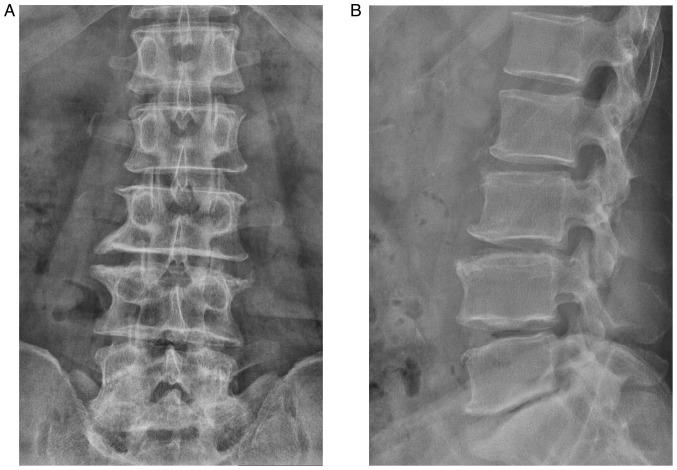

Spinal gout is a relatively rare disease characterized by significant clinical symptoms. In the current study, the first case of spinal gout with tophus in the intervertebral foramen, which perfectly mimicked degenerative lumbar disc disorders, was presented. The patient was a 57-year-old man with a medical history of gout who had suffered from progressive neurological deterioration for the last 12 months. Imaging examination revealed bilateral stenosis in the L5/S1 intervertebral foramen, mimicking degenerative lumbar disc disease. Nerve root radiculography and blocking were performed and the neurological symptoms were completely relieved. Open surgery was further performed and unexpectedly, the intra-operative findings were amorphous chalky white lesions. Histopathology confirmed the diagnosis of spinal gout. After surgery, the patient was prescribed a medication and achieved complete remission of clinical symptoms. No deterioration was found at the 1-year follow-up. To the best of our knowledge, this is the first report of spinal gout tophus in intervertebral foramen in the literature. It was concluded that, although intraspinal tophaceous gout is relatively rare, orthopedic surgeons should take it into consideration as a differential diagnosis, particularly if the patient has a medical history of gout. Early diagnosis and timely medical management may possibly be able to avoid neurological compromise and the need for surgery.

脊柱痛风是一种相对罕见的疾病,具有明显的临床症状。在本研究中,报告了首例椎间孔有痛风石的脊柱痛风病例,该病例酷似退行性腰椎间盘疾病。患者为一名57岁男性,有痛风病史,在过去12个月中出现进行性神经功能恶化。影像学检查显示L5/S1椎间孔双侧狭窄,类似退行性腰椎间盘疾病。进行了神经根造影和阻滞,神经症状完全缓解。进一步进行了开放手术,术中意外发现为无定形的灰白色病变。组织病理学确诊为脊柱痛风。术后给患者开了药,临床症状完全缓解。1年随访未发现病情恶化。据我们所知,这是文献中首例关于椎间孔脊柱痛风石的报告。结论是,尽管脊髓痛风石相对罕见,但骨科医生应将其作为鉴别诊断考虑,特别是如果患者有痛风病史。早期诊断和及时的医疗管理可能能够避免神经功能损害和手术需求。